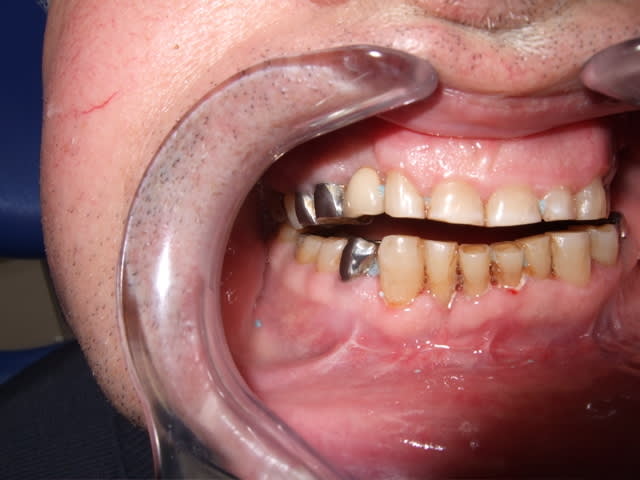

Bon je suis bien embêté avec mon grand père et je vous laisse juger par les photos.

- fractures multiples suite à accident cheval

- opéré en urgence avec complications majeures car sous aap

- impossible de transférer dans un service de chir max, opéré par ORL (ndlr)

- pas de blocage inter maxillaire, ne me demandait pas pourquoi

- retrait des ligatures et chirurgien septique me laisse un courrier en me demandant de meuler les molaires pour rattraper le décalage.

Bon je fais une petite mesure rapide : 38 = 1,5mm de hauteur coronaire, et béance de près de 4mm au maximum

bref, il est passé d'un bourrin à l'autre!!

je crois que ça relève de la maxillo, et certainement pas d'un meulage!

il y a quand même une fracture importante pas du tout réduite à droite.

les inlays, pourquoi pas, mais il faut voir d'abord ou sont les condyles.